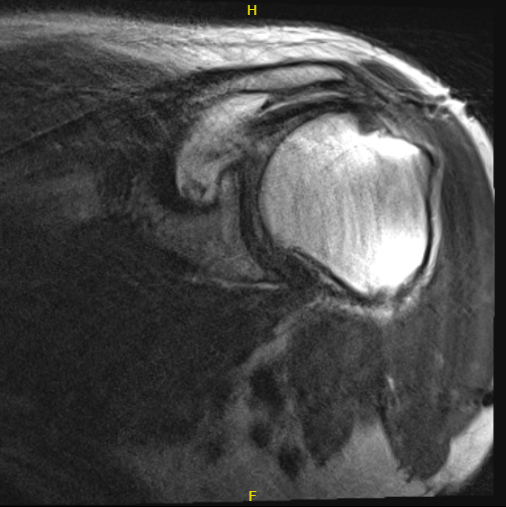

He presented his MRI to me, and we reviewed it. Impression as follows: Status post rotator cuff repair with marked metal artifact slightly limited examination. Suggestion of at least partial tearing of the supraspinatus tendon.

Consider CT arthrogram or ultrasound for further evaluation. High-grade partial tearing of the infraspinatus tendon with possible full-thickness component. Suggestion of biceps tenodesis.

MRI of the left shoulder